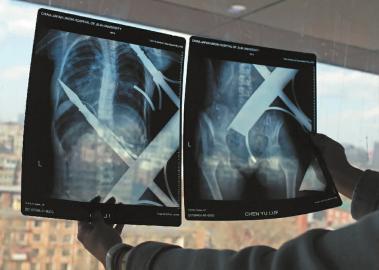

X光片顯示一根鋼筋將小女孩的右側肩膀刺穿,另外一根則從后背腰部以上靠近脊椎的地方穿入 白石 攝

在急診室的病床上,李紅旭看到了小雨?!八龗熘跗?,意識比較清醒?!边M一步觀察,李紅旭一時說不出話來———一根鋼筋穿透小雨右側肩膀,另一根則從后背腰部以上靠近脊椎的地方穿入,從小雨左肩部分穿了出來。兩根鋼筋由兩根角鐵連接,距離事發,小雨背著這片鐵柵欄已經近7個小時了。